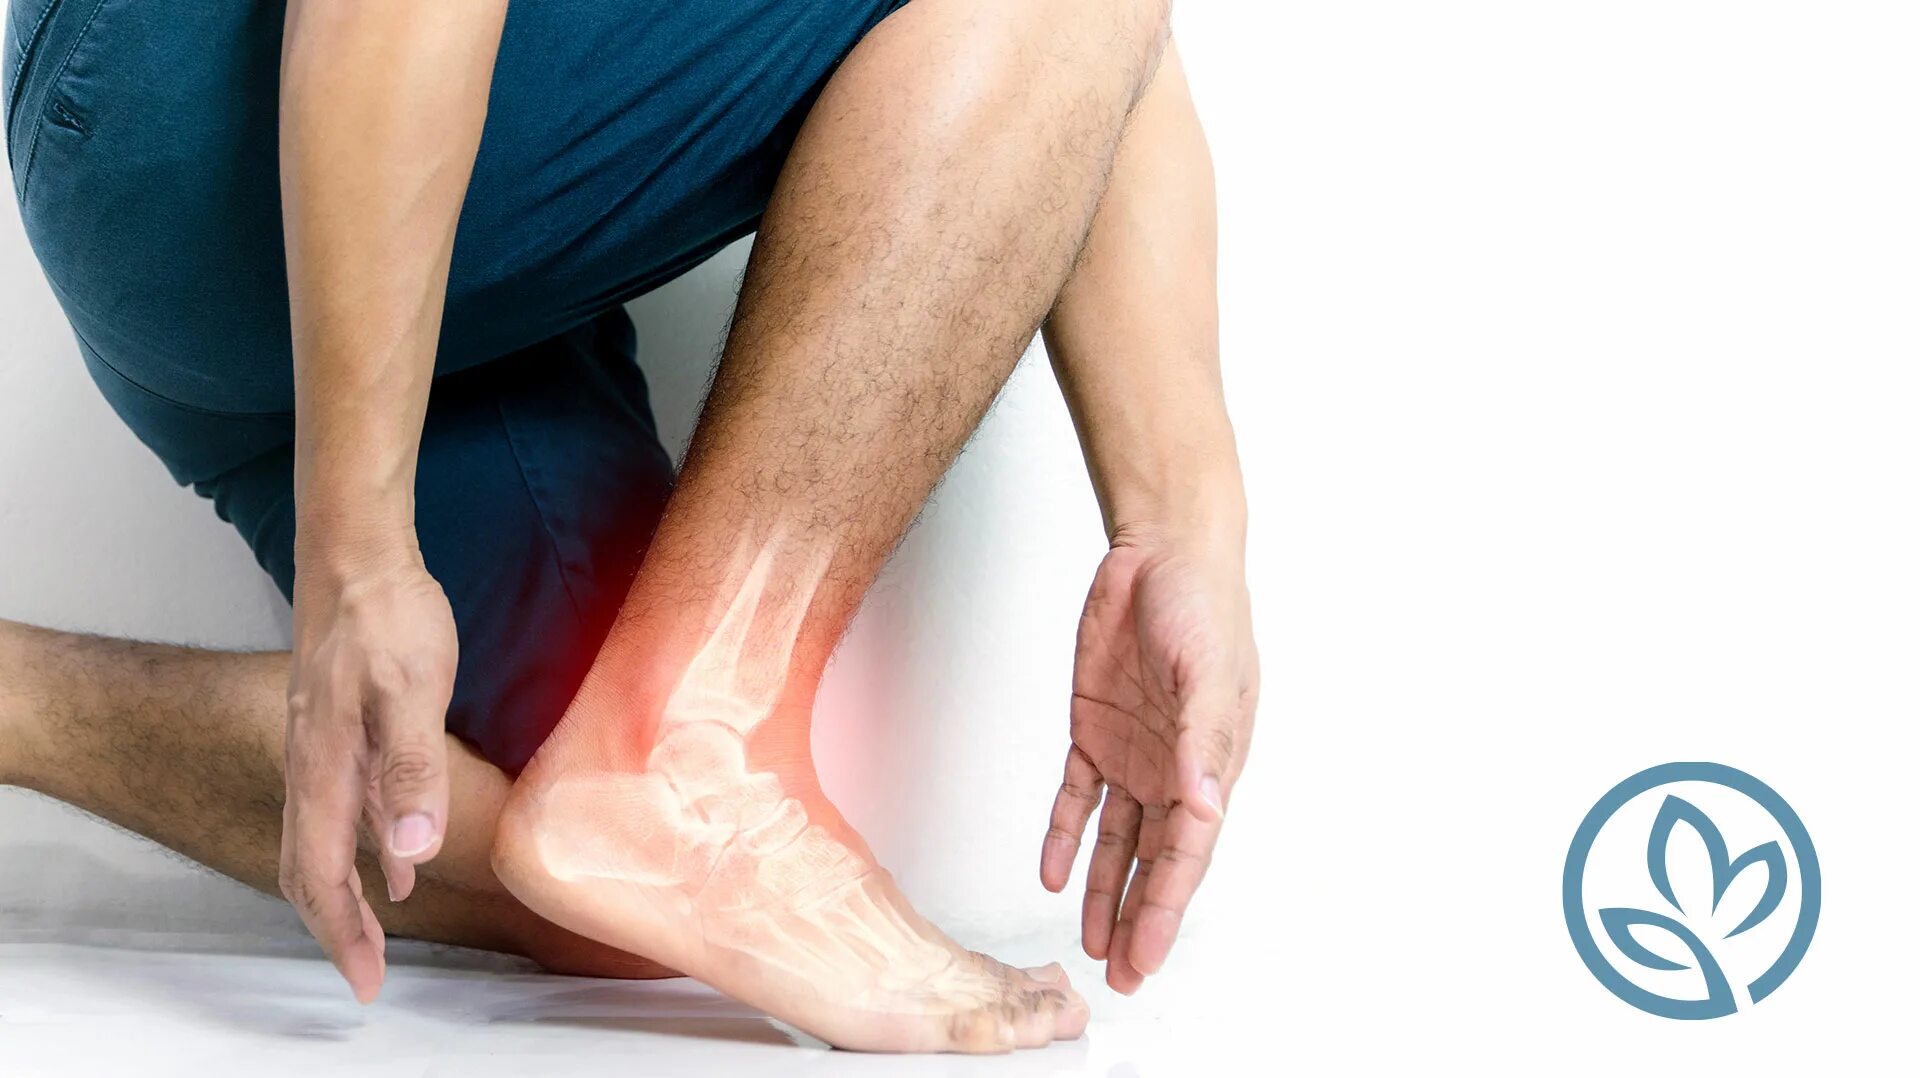

Артроз пяточных суставов